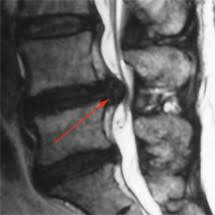

Bandscheiben op lws 4 5. Sie kommen meist zwischen den Wirbeln LWK Lendenwirbelkörper 45 und LWK 5SWK 1 Sakralwirbelkörper vor an der vorletzten und letzten Bandscheibe. Bandscheibenvorfälle sind Teil einer natürlichen Abnützung des Gewebes. Drückt der Gallertkern auf einen Rückenmarksnerven leiden Betroffene unter starken Rückenschmerzen die teilweise bis in Arme und Beine ausstrahlen.

Ursachen Diagnose und Therapie. Wie der Bandscheiben-Vorfall Prolaps ist die Bandscheiben-Vorwölbung Protrusion besonders häufig in der Etage bei L4L5 zwischen dem 4.

Wenn die Physiotherapie und Medikamente nicht mehr helfen und die Schmerzen zu stark sind oder wenn der Druck auf die Nerven Ausfälle verursacht Taubheit Muskelschwäche Lähmung sollte eine Operation in Betracht gezogen werden. Bandscheibenvorfall LWS Übungen - Hier findest du 5 effektive Übungen bei einem Bandscheibenvorfall in der Lendenwirbelsäule inkl. Es geht mir zur Zeit nicht gut mache mir auch große Sorgen wie es wird in den nächsten Tagen und Wochen mit den Schmerzen und Beschwerden. Ich wurde am 4. Frank aus München in. Probieren Sie es selbst aus. Sie kommen meist zwischen den Wirbeln LWK Lendenwirbelkörper 45 und LWK 5SWK 1 Sakralwirbelkörper vor an der vorletzten und letzten Bandscheibe. Die Bandscheiben der Wirbelsäule übt eine Art Stossdämpferfunktion aus und dient der Elastizität und der Beweglichkeit der Wirbelsäule. Lendenwirbel und dem 5.

Die Bandscheibenvorfälle an der Lendenwirbelsäule sind die häufigsten Bandscheibenvorfälle an der Wirbelsäule. In der Regel verschwinden die Schmerzen zwar nach der OP es kann aber immer sein dass sich Symptome nicht zurückbilden. Wenn die Physiotherapie und Medikamente nicht mehr helfen und die Schmerzen zu stark sind oder wenn der Druck auf die Nerven Ausfälle verursacht Taubheit Muskelschwäche Lähmung sollte eine Operation in Betracht gezogen werden. 3053 Beiträge ø047Tag Hallo vor 1 Woche hatte ich eine große Bandscheiben-OP. Wie der Bandscheiben-Vorfall Prolaps ist die Bandscheiben-Vorwölbung Protrusion besonders häufig in der Etage bei L4L5 zwischen dem 4. Bandscheibenvorfall 4-5 Lendenwirbel Hey S-A2011 danke für Deine Erzählung. Alleine in Deutschland werden jährlich ungefähr 150000 Bandscheibenvorfälle operativ behandelt.